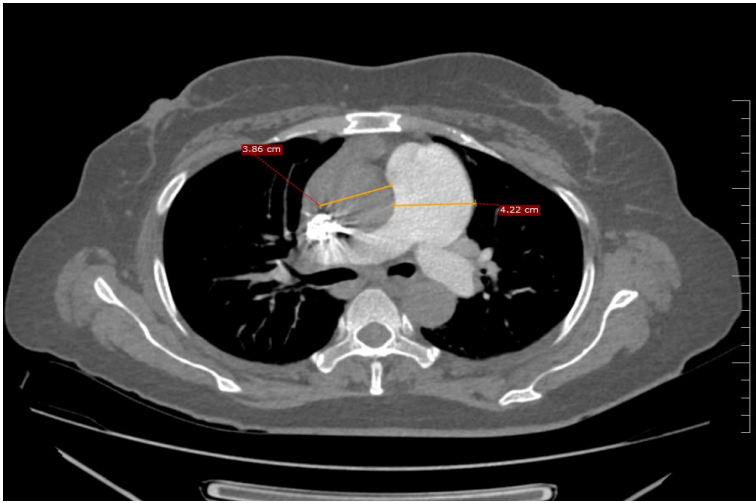

2D ECHO was done and it showed normal Left ventricle systolic function, ejection fraction 60%with moderate pulmonary hypertension (RVSP = 51mmhg). CT Thorax was done and it showed prominent main pulmonary artery and its branches with diffuse mosaic attenuation in bilateral lung fields, mild cardiomegaly and bilateral pleural effusion. Evaluation for pulmonary hypertension was done. D-dimer was 1.46 micro gram /ml. CT pulmonary angiogram was done and it showed no evidence of pulmonary thromboembolism. Anti-nuclear antibody (immunofluorescence) was negative. Thyroid profile was done and it showed TSH < 0.01 m IU/L free T3 11.6 pg/mL freeT4 4.7 ng/dL and anti-thyroid peroxidase >1000 IU/ml. Ultrasound of thyroid showed bilateral lobes of thyroid appearing bulky, heterogenous with increased with vascularity. Patient was diagnosed to have Grave’s disease and patient was started on oral carbimazole 5 mg twice a day.

Fig 1: Ct Chest Showing Dilated Main Pulmonary Artery With Reversal Of Aorta Pulmonary Ratio